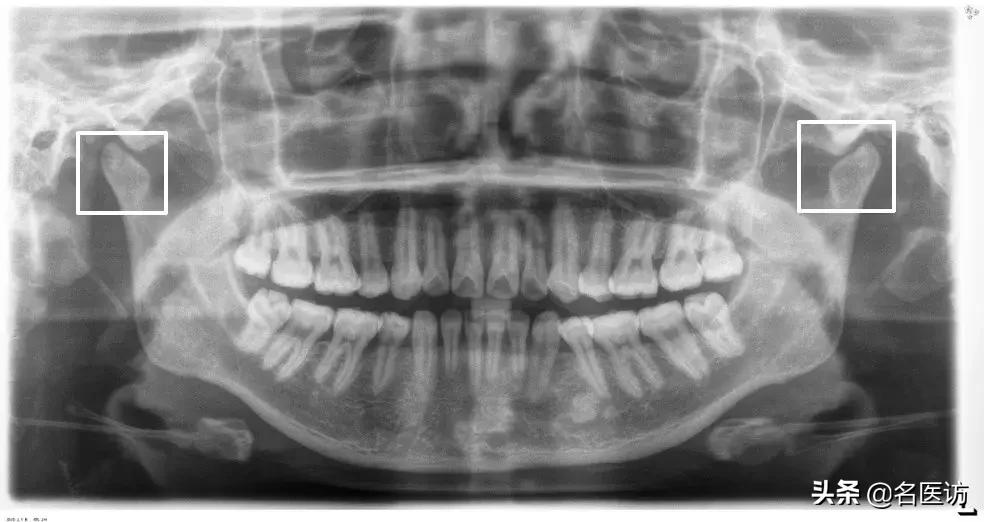

髁突磨损

全景片观察的主要是颞下颌关节的对称性和髁突的形态,如果关节严重不对称或髁突有明显磨损,需要去做进一步的详细检查,不能贸然开始做矫正。